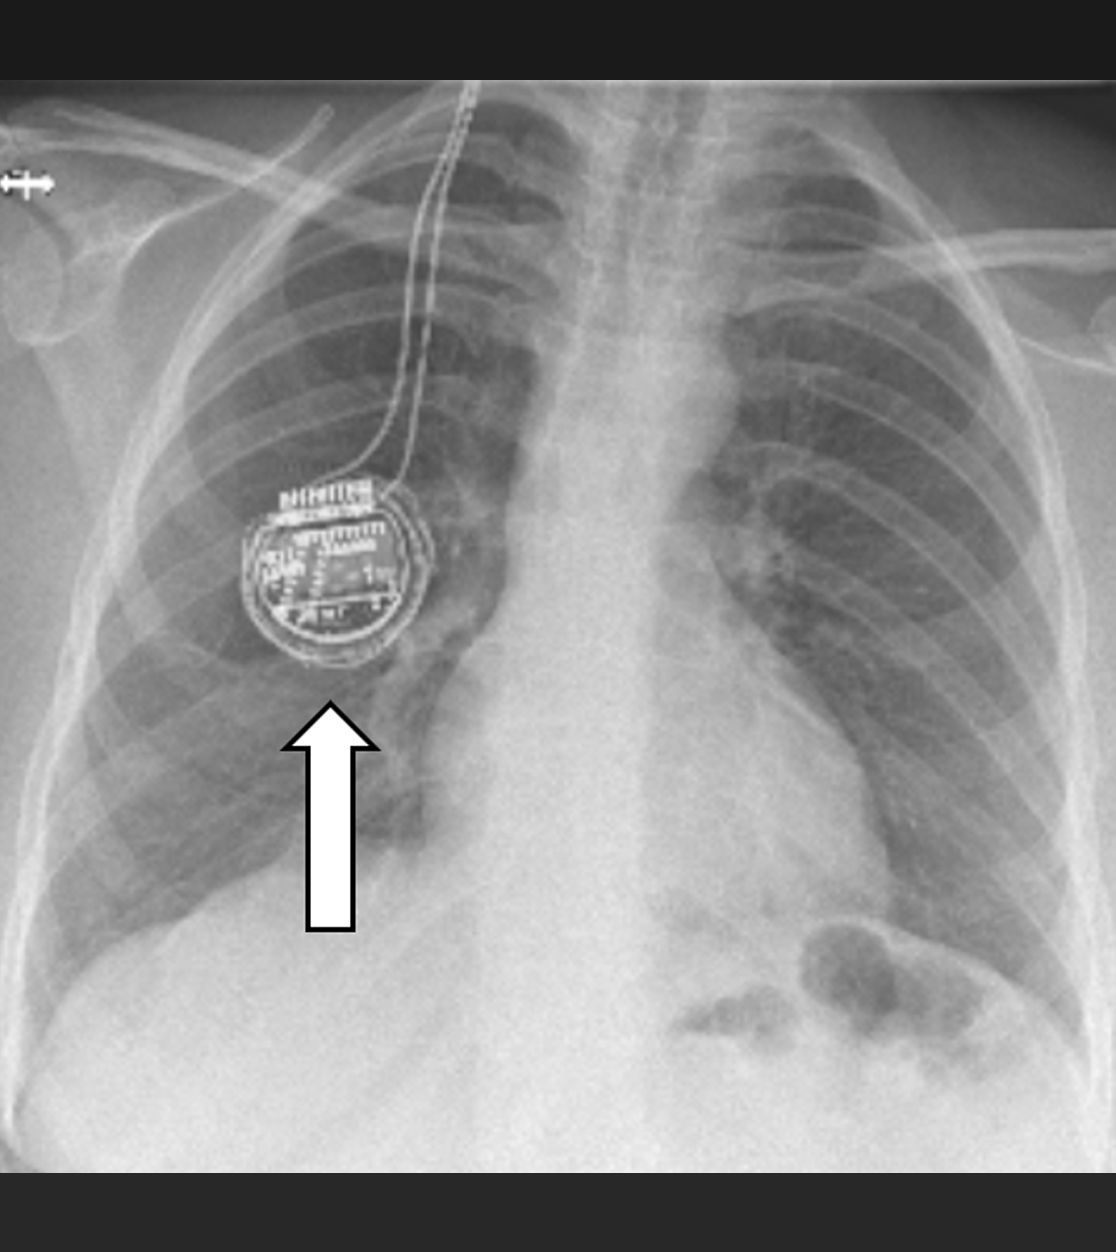

Bei der Rückenmarkstimulation wird in der Wirbelsäule eine Elektrode platziert. Über diese werden elektrische Impulse an das Rückenmark abgegeben. Die Elektrode ist mit einem Impulsgeber (vergleichbar mit einem Herzschrittmacher) verbunden. Das operative Verfahren gliedert sich in zwei Abschnitte: Im ersten Eingriff erfolgt, unter örtlicher Betäubung und Röntgenkontrolle, die Platzierung der Elektrode im Rückenmarkskanal. Im Anschluss erfolgt eine Testphase. Ziel ist es, die Abdeckung des Schmerzareals durch die Stimulation und die daraus resultierende Schmerzreduktion zu testen. Bei zufriedenstellendem Ergebnis wird in einem zweiten Eingriff der Impulsgeber unter die Haut implantiert.

Die über die Elektrode abgegebenen Impulse bewirken im Bereich des Rückenmarks eine Unterbrechung/Verminderung der Schmerzleitung der Nerven. Hierbei ist es notwendig, bei jedem Patienten individuell die notwendigen Stimulationsparameter festzulegen. Die schmerzreduzierende Wirkung der Neurostimulation kann in einem zweiten Schritt die Verringerung der Schmerzmedikation nach sich ziehen.

Röntgenbild zur Rückenmarkstimulation

Am Bauch implantierte Medikamentenpumpe (Pfeil)